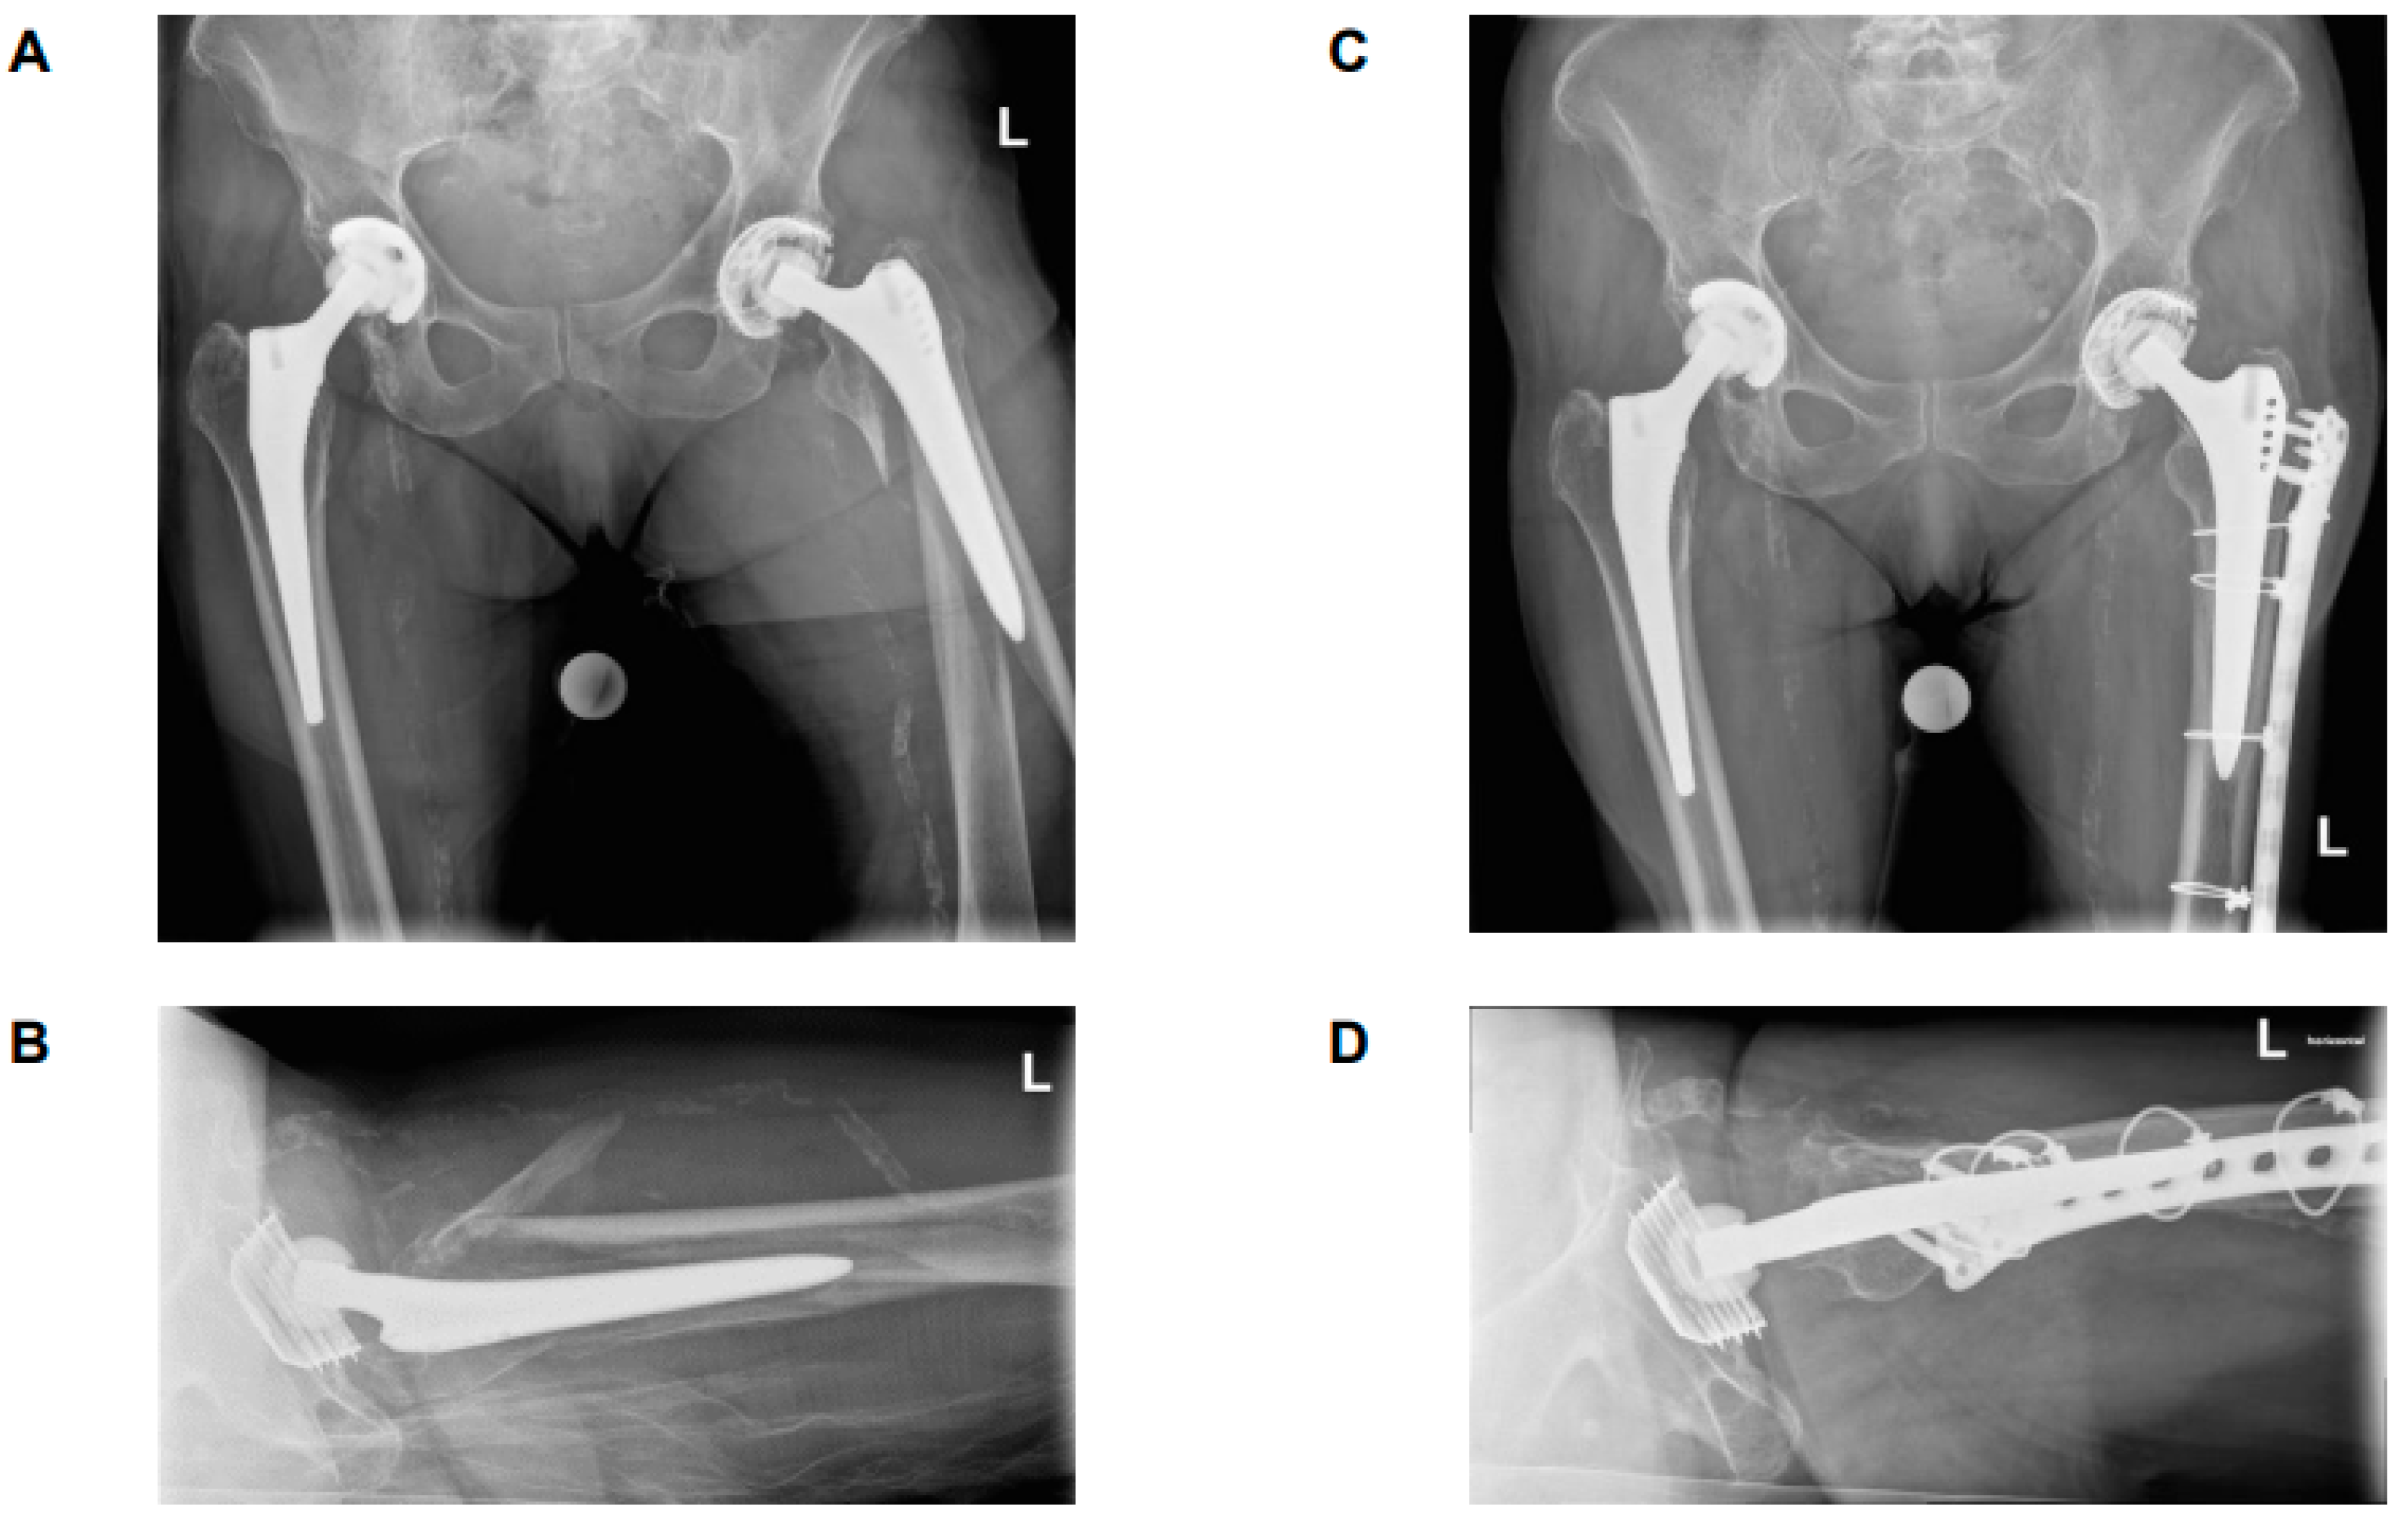

4.1. B2 ‘Stable’ Stems

4.2. B2 ‘Loose’ Stems